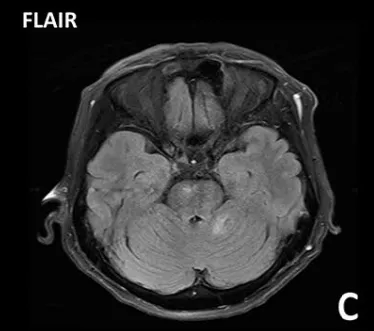

非脑干高级别胶质瘤的特征性磁共振成像表现包括T1加权像低信号、T2加权像皮质和白质高信号(表现为肿瘤浸润和血管源性水肿)以及不规则的强化。弥漫性内生性桥脑胶质瘤通常表现为一个大的、扩张性脑干肿块,中心位于脑桥,占据其三分之二。病变通常在T1加权像上呈低信号或等信号,边缘模糊不清,在T2加权图像上呈模糊的高信号,这反映了肿瘤的浸润性。但在液体衰减反转恢复序列图像上,弥漫性内生性桥脑胶质瘤经常显得相对均匀。这些肿瘤的对比增强可能是可变的,但无明确的预后意义。

弥漫性内生性桥脑胶质瘤是常见于5岁至10岁儿童的高度恶性、进展迅速的侵袭性肿瘤。中位生存期约为9个月。临床表现通常是颅神经功能障碍、长束征和共济失调。此外,还可能存在继发于脑室梗阻的颅内压升高迹象。症状持续时间通常很短。1型神经纤维瘤病患者的病程可能相对缓慢。弥漫性内生性桥脑胶质瘤的诊断标准通常基于明确的磁共振成像表现,因此,活检常被视为不必要。

弥漫性内生性桥脑胶质瘤

治疗弥漫性内生性桥脑胶质瘤的挑战在于其恶性的高级别组织学特征及其位于脑干中心区域这一特殊性。目前的重要治疗手段是放疗,手术仅限于活检,而活检主要用于磁共振成像表现不典型、不确定,或当研究方案有此要求时。立体定向活检已被证明是安全的。化疗在弥漫性内生性桥脑胶质瘤管理中的作用仍在评估中。